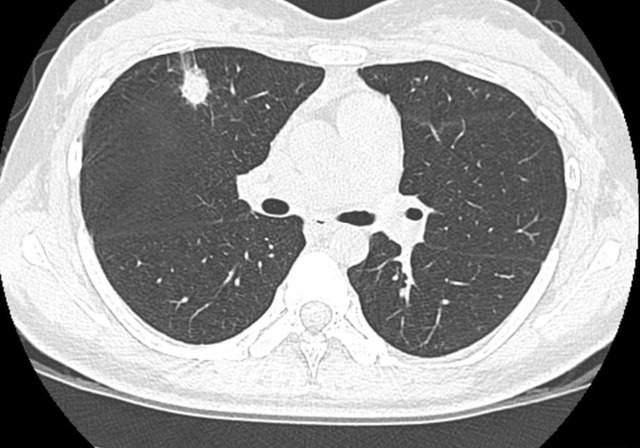

因为工地的粉尘比较多,导致李大叔经常感觉到喉咙不舒服,在4年前的时候发现自己咳嗽越来越严重,就去医院进行检测。检测的结果让李大叔大吃一惊,原来自己的肺部竟然出现了小的病灶面积,大约在1.26×0.83左右。